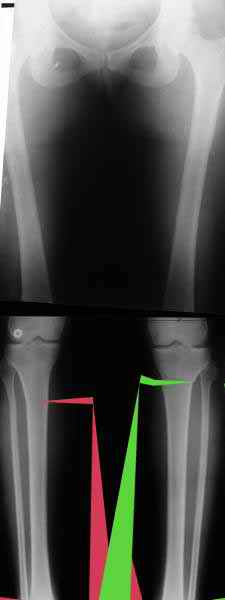

AVM> Александр, а не могли бы вы представить ваши схемы расчета? С учетом

Вот, с учетом и без учета, и на разных уровнях...

Саша Артемьев, может, для данного случая свой вариант нарисуешь?

Из приведнной схемы не совсеим понял что означают разноцветные линии.

И зачем латерализация периферического фрагмента. Я всегда делаю медиализацию. См схему. И для данного случая медиализация подходит как нельзя лучше.

a> Из приведнной схемы не совсеим понял что означают разноцветные линии.

Черные - это нынешняя механическая ось. Красные - это планируемая правильная ось.

a> И зачем латерализация периферического фрагмента.

;-) Читайте Палея. Стр. 114-115.

a> Я всегда делаю медиализацию. См схему. И для данного случая

Медиализация - это чисто эстетический прием, как я понимаю. Поскольку если делать остеотомию ниже вершины деформации, для восстановления оси надо делать смещение по ширине, в данном случае как раз латерализацию.

А вот на схемке без осей - там на разных уровнях (который правильнее?) устранение варуса чисто открытым клином без медиализации-латерализации. Если как-то так сделать - этого недостаточно будет?